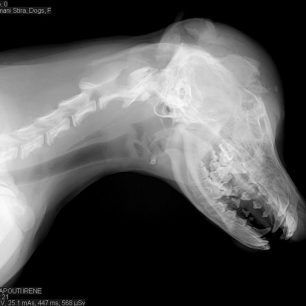

Με ποινή φυλάκισης 15 μήνες με διετή αναστολή και χρηματική ποινή 6.000 ευρώ καταδικάστηκε σήμερα από το Α’ Τριμελές Πλημμελειοδικείο Χαλκίδας ο Κώστας Λιάπης που στις 17 Ιουλίου του 2014 στα Νέα Στύρα Εύβοιας κοπάνησε με μια καρέκλα στο κεφάλι έναν αδέσποτο θηλυκό σκύλο, τη Μάγκυ, που ήταν μόλις 3,5 μηνών.

Ο δολοφόνος του ζώου ενώπιον τουριστών και περαστικών ξεκάθαρα δελέασε το νεαρό σκυλί με τροφή ώστε να τον πλησιάσει με αποτέλεσμα από το χτύπημα το κουτάβι να μείνει κλινικά νεκρό αφού θρυμματίστηκαν τα οστά του κρανίου του έτσι η κτηνίατρος Ταπούτη, η οποία το εξέτασε λίγες ώρες αργότερα αναγκάστηκε να του κάνει ευθανασία.